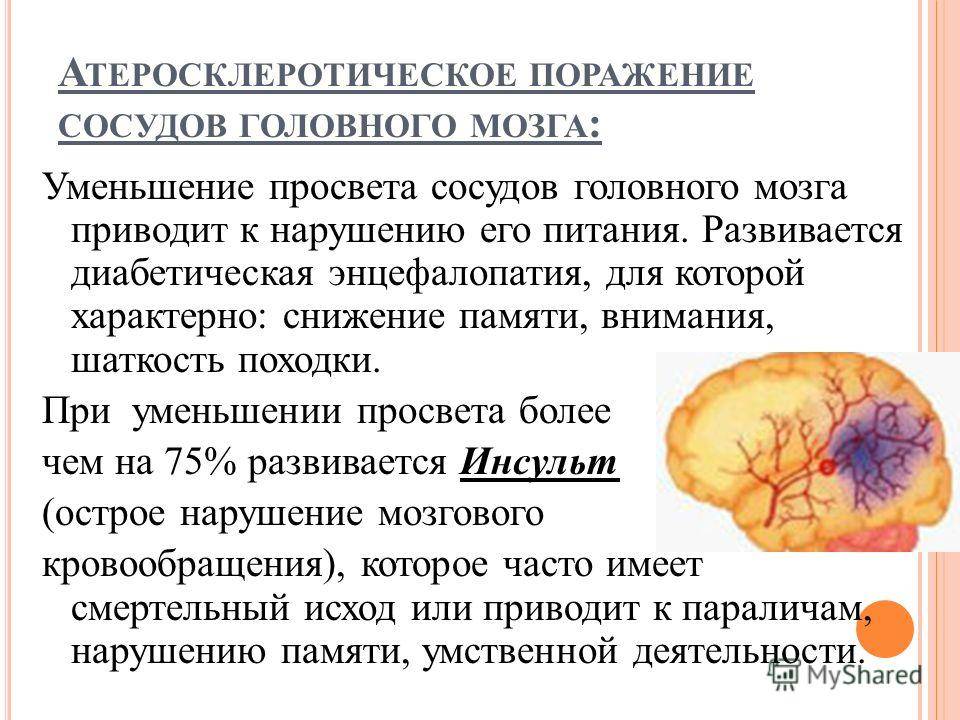

Контролируйте уровень сахара в крови - повышенный уровень сахара может быть связан с нарушениями кровообращения в головном мозге.